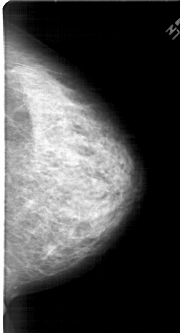

A_1453_1.RIGHT_MLO

RIGHT_MLO LINES 6871 PIXELS_PER_LINE 3496 BITS_PER_PIXEL 12 RESOLUTION 43.5 NON_OVERLAY